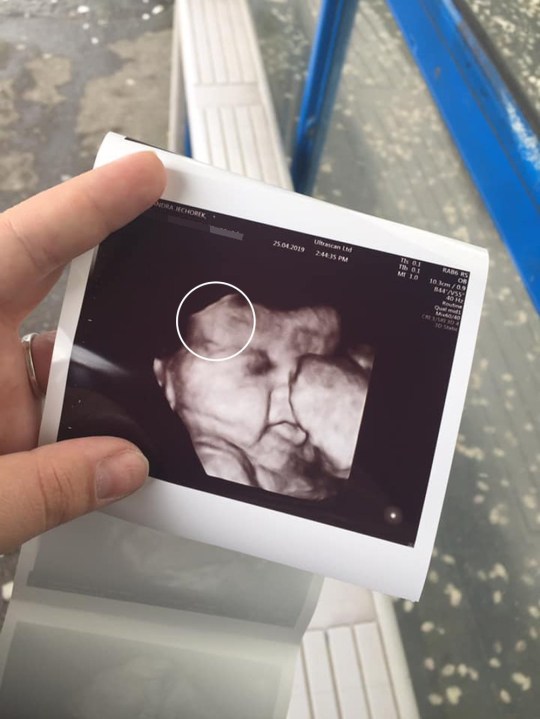

Trong lần siêu âm ở tuần thứ 34 tuần của thai kỳ, bà mẹ Alexandra Jechorek, đến từ Dublin (Ireland), đã bị sốc nặng khi được bác sĩ chỉ cho thấy con gái của chị có một mái tóc dày. Và 6 tuần sau đó, bé gái Maya chào đời đã khiến cả ê-kíp sinh phải kinh ngạc vì mái tóc dày, bóng mượt của mình.

Chị Alexandra cho biết: "Chúng tôi biết chúng tôi sắp có một cô con gái, vì vậy cứ đúng hẹn là chúng tôi lại đi siêu âm để xem con phát triển như thế nào. Ở tuần thứ 34, khi bác sĩ cho xem màn hình siêu âm, tôi đã không thể tin được vào mắt mình. Một em bé nhỏ xíu nhưng đã có rất nhiều tóc. Tôi không biết làm thế nào mà điều này có thể xảy ra được, vì thông thường trẻ sơ sinh rất ít tóc. Ngay cả đứa con lớn Kadin của tôi khi mới sinh ra cũng bị hói đầu".